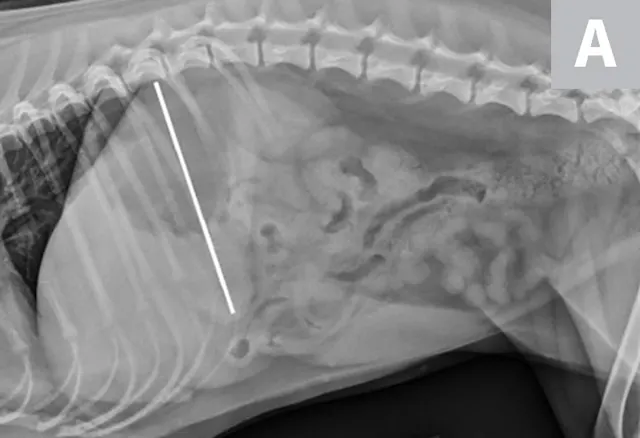

FIGURE 1A

Right lateral radiographs of a clinically normal dog (A) and an 11-year-old neutered male dachshund with diabetes mellitus (B). The dog with diabetes mellitus has a pendulous abdomen and an enlarged liver (ie, hepatomegaly) with rounded margins that extend caudal to the costal arch (B; arrows). The gastric axis (solid lines; aligned with the gastric fundus dorsally to the antrum ventrally) is parallel to the ribs in the clinically normal dog but caudally displaced in the dog with hepatomegaly. Common differential diagnoses for generalized hepatomegaly are vacuolar hepatopathy due to endocrinopathies or other metabolic disease (eg, lipidosis), infectious and noninfectious inflammatory disease, neoplasia, storage disease, and venous congestion.